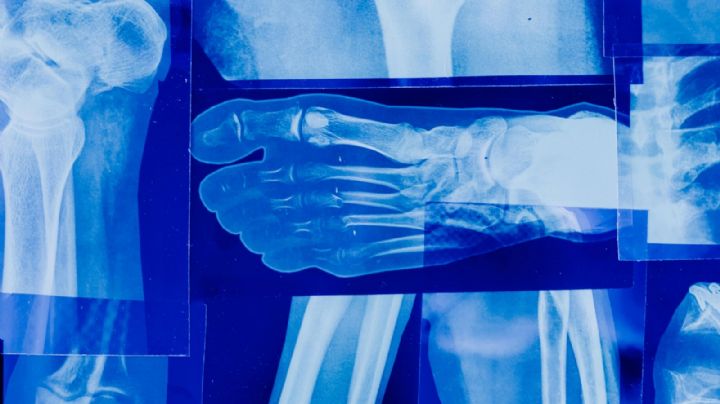

SALUD Síndrome de Guillain-Barré: ¿Cómo se contagia y cuáles son sus síntomas? Así puedes detectarlo 7/3/2024 | ¿Qué el es Síndrome de Guillain-Barré? Esto son sus síntomas y formas de diagnóstico.